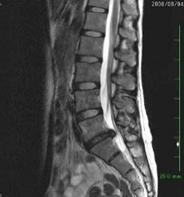

2.腰椎椎間板ヘルニア

椎間板は中心が柔らかい髄核とその周りを繊維性軟骨組織からなる繊維輪で構成され、椎間板は椎骨間で衝撃を吸収するクッションのような役割を果たします。

クッションの表面が破れた状態、すなわち椎間板・線維輪に亀裂が入って内部の髄核が飛び出した状態が椎間板ヘルニアです。

通常、激しい腰痛と片側の下肢痛・しびれ感を引き起こします。

疼痛やしびれ感の部位は、圧迫される神経によって異なります。

神経症状の強い場合は障害神経の支配筋に運動麻痺を生じます。

神経根の圧迫による完全な運動麻痺の回復は困難であり注意を要します。